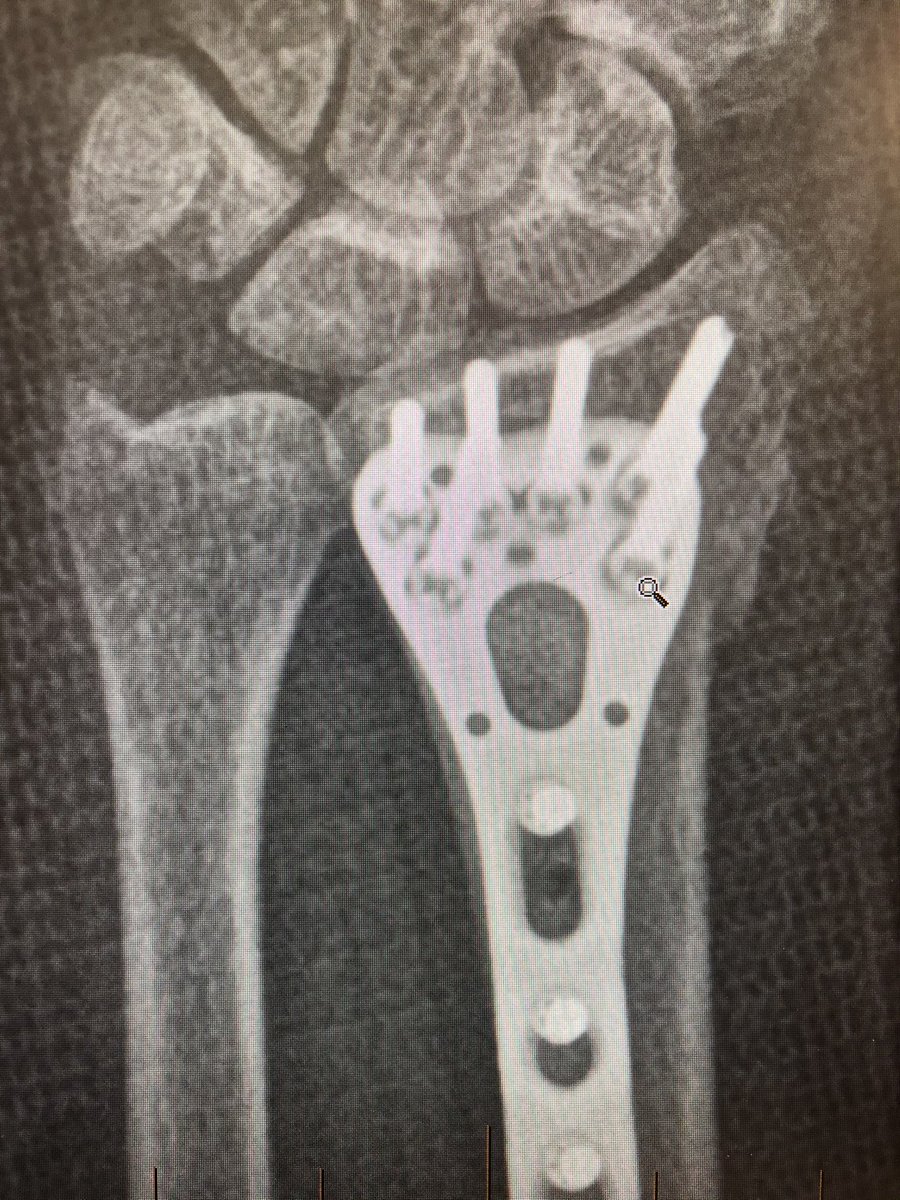

Point 2:

The dorsal metaphyseal comminution. The dorsal cortex fragment is ‘fallen in’ inside the osteoporotic metaphyseal void.

I addressed this after plating finished, made a 4.5 mm drill hole in the ‘window’ of the plate to push the fragment and fill in graft substitute.